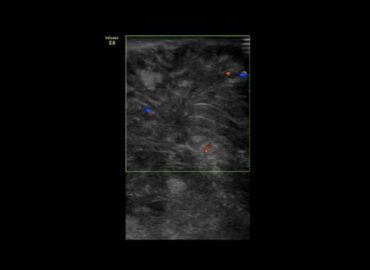

Paciente de 14 años de edad, que consulta por edema palpebral izquierdo de 15 dias de evolucion.

Edema palpebral de ojo izquierdo